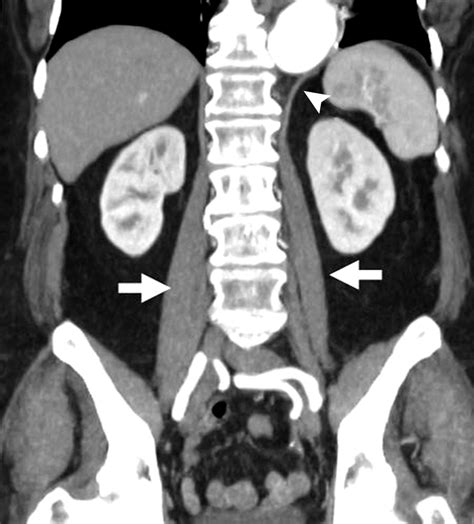

Physicians often use diagnostic imaging to evaluate the integrity of the diaphragm right crus, particularly in cases of suspected diaphragmatic hernia or thoracic trauma. MRI (Magnetic Resonance Imaging) and high-resolution CT scans are the gold standards for visualizing these deep muscular attachments. These scans allow clinicians to observe the thickness and symmetry of the crura, which can be indicators of overall diaphragmatic health.

During an assessment, a clinician might observe:

• Muscle Atrophy: Thinning of the crus fibers can weaken the esophageal sphincter.

• Hypertrophy: Sometimes the crus thickens due to chronic strain or high intra-abdominal pressure.

• Structural Deviations: Variations in the size of the hiatal opening can predispose an individual to sliding hiatal hernias.